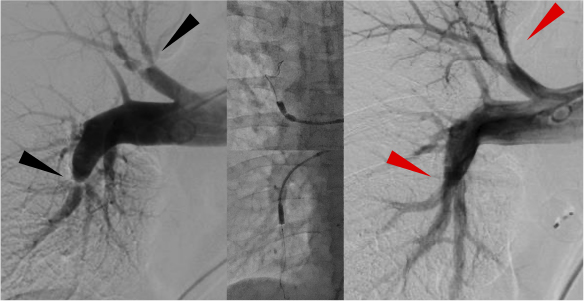

CTEPHとは慢性血栓塞性肺高血圧症(Chronic thromboembolic pulmonary hypertension)の略であり、肺血管内に血栓が形成され慢性化した状態です。治療法には、薬物療法、また中枢型では外科的な手術(肺動脈内膜剥離術)があります。当院では末梢型では埼玉県立循環器呼吸器病センターのBPA指導医のもとで修業を積んで経皮的肺動脈形成術(Balloon pulmonary angioplasty:BPA)を行えるようになりました。

CTEPHではカテーテル治療(BPA)により

CTEPHではカテーテル治療(BPA)により息切れや呼吸困難が緩和されます